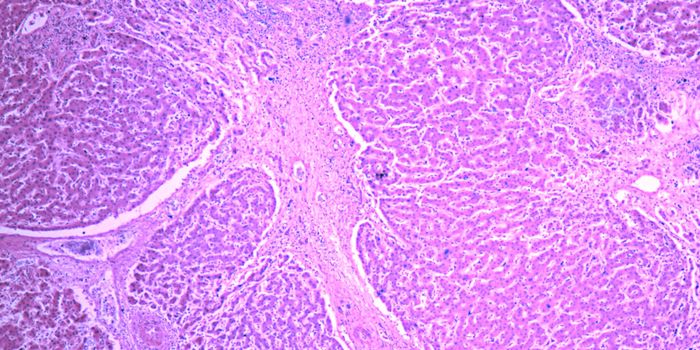

Follow a curation of discoveries and updates in immunology focusing on immune responses to infectious disease, structure and function, and developments in the defense against infection.